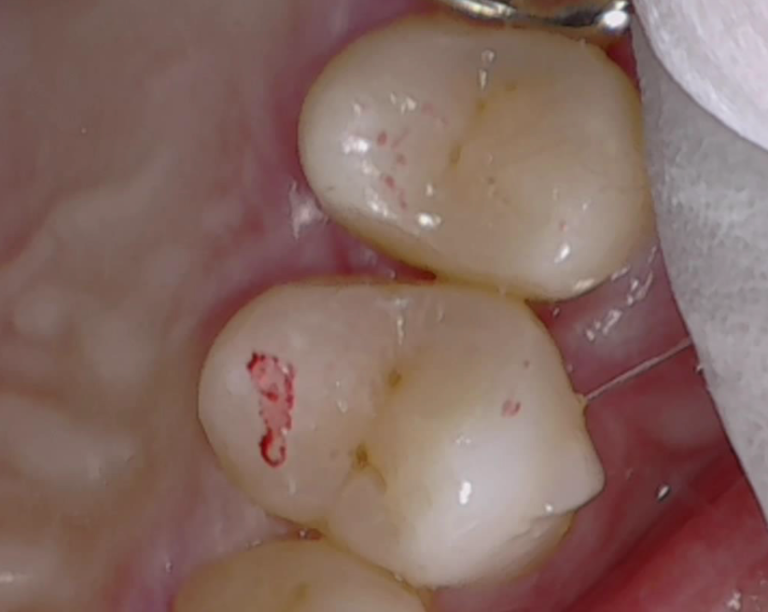

29歳女性

歯が黒いのでみてほしい

口腔内写真と歯科用レントゲン

口腔内所見では少し歯が黒いのかな?また、レントゲンでもはっきりとは映ってはいないが、診査診断を行うことで早期の治療を話をした。